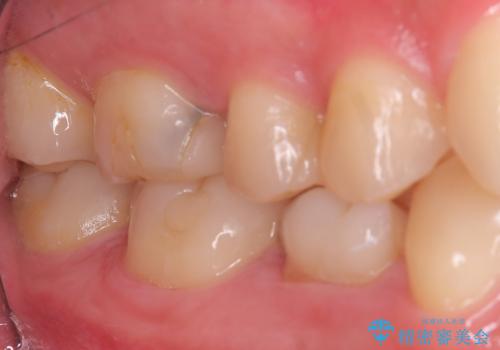

対合歯との咬合関係において、右下7番目と6番目の被せものの連結部がたわみやすい環境にあったため、ブリッジの新製ではなくインプラント治療を行いすべての歯を単冠仕上げとすることにしました。

何度も右下6、7間でブリッジが折れてしまうとのことでした。対合歯とブリッジの連結部が強く当たりたわみやすい状態でした。破折しずらい金属を使用したブリッジの選択もありましたが、支台歯(右下7)が失活歯場合、破折リスクが高く、破折してしまった場合にまたブリッジを外しての再治療になってしまう可能性を説明したところ、全て単冠仕上げとできるインプラント治療を希望されました。

右下5番のクラウンは、ブリッジを切断しそのまま使用していただいています。